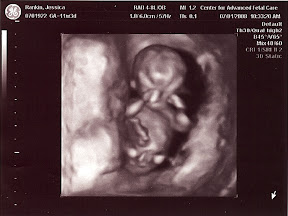

This is a long awaited and greatly prayed for moment for all of us. We have been very excited and God has shown us so much mercy as the pregnancy has progressed. We saw the heartbeat at that first ultrasound which gave us confidence in the blessing the Lord has bestowed upon us. At our first Dr.'s appointment, 8 weeks, this baby had the earliest heartbeat our Dr. has ever heard externally with a doppler, another glorious mercy given to us. And then yet again at the 11 week mark the ultrasound revealed that we have been blessed with a healthy baby.

It was such a relief to see the miracle of life, perfectly created by God inside mommy. Though we know that every child is perfectly designed by God, we were very thankful to hear that he had blessed us with a healthy baby. Mom is doing great and the Dr. has said this is a textbook, perfect pregnancy! Praise be to God.